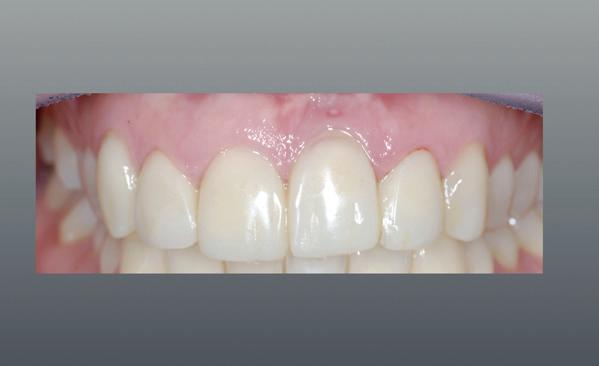

1. Studiofoto intake

aan zijn gebit gedaan behalve pappen en nathouden. Tandheelkundige zorg werd enkel verleend wanneer er zich een probleem voordeed (afbeelding 1, 3, 5).

Na afronding van de eerste twee behandelstappen werd parodontale stabiliteit bereikt, zoals waarneembaar op de parodontiumstatus en (röntgen)foto’s (afbeelding 6, 8). De patiënt toonde aantoonbare verbetering in mondhygiëne (afbeelding 4) en bleef gemotiveerd om de behandeling voort te zetten.